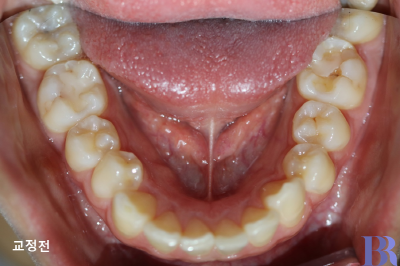

발치교정 : 하악 교정전 모습

아래치아 모습입니다.

아래치아는 발치없이 교정이

마무리됐음을 알 수 있습니다.